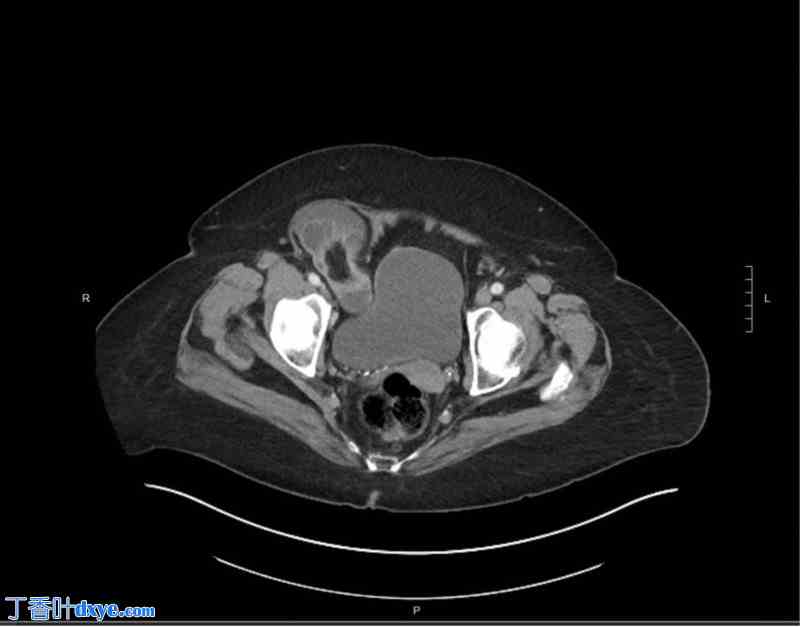

一位85岁女性因右侧腹股沟疼痛就诊。除轻度痴呆和BMI为32外,患者身体健康。右侧腹股沟可见可复位肿块,左侧正常。医生建议患者在镇静下行开放性修补术。术中,切除圆韧带后,发现腹股沟底非常薄弱,遂使用一块网片进行重建。患者术后恢复良好,直至术后两周因肠梗阻就诊于急诊室。CT扫描(图1)显示嵌顿性股疝。

图1

该CT扫描显示右侧股疝,部分小肠嵌顿于疝缺损处。